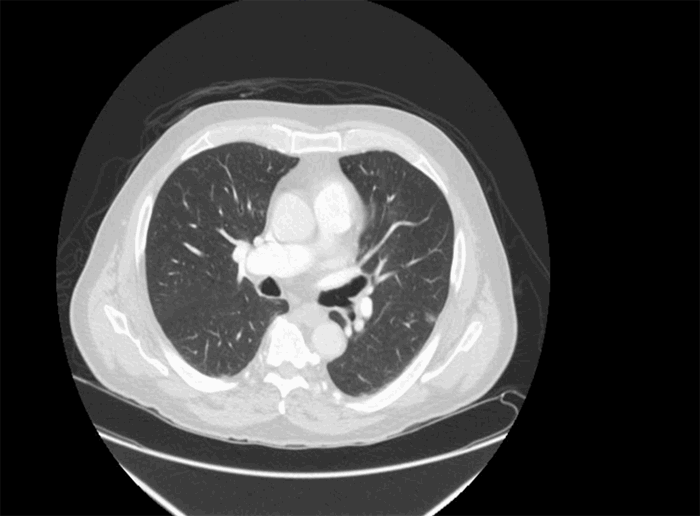

On laboratory examination, his white blood cell count (WBC) was 6900/uL, with lymphopenia of 19.3 percent (normal: 22 to 44 percent). D-dimer was initially normal at 458 ng/mL (normal: <500 ng/mL) but continued to rise, with a peak at 3750 ng/mL. Serum fibrinogen level was elevated to 1034 mg/dL (normal: 150–400 mg/dL). Tests for respiratory syncytial virus and influenza were negative. Chest X ray showed bilateral linear lung atelectasis and scarring. CT angiogram of the chest showed signs of emphysema and chronic bronchitis (Figure 1a). A nasopharyngeal swab was sent for polymerase chain reaction (PCR) testing and was positive for COVID-19.

Figure 1. Case 1 CT imaging (a) CT angiogram of the chest showed signs of emphysema and chronic bronchitis; (b) CXR consistent with acute respiratory distress syndrome; (c) abdominal X-ray showing generalized large bowel dilatation